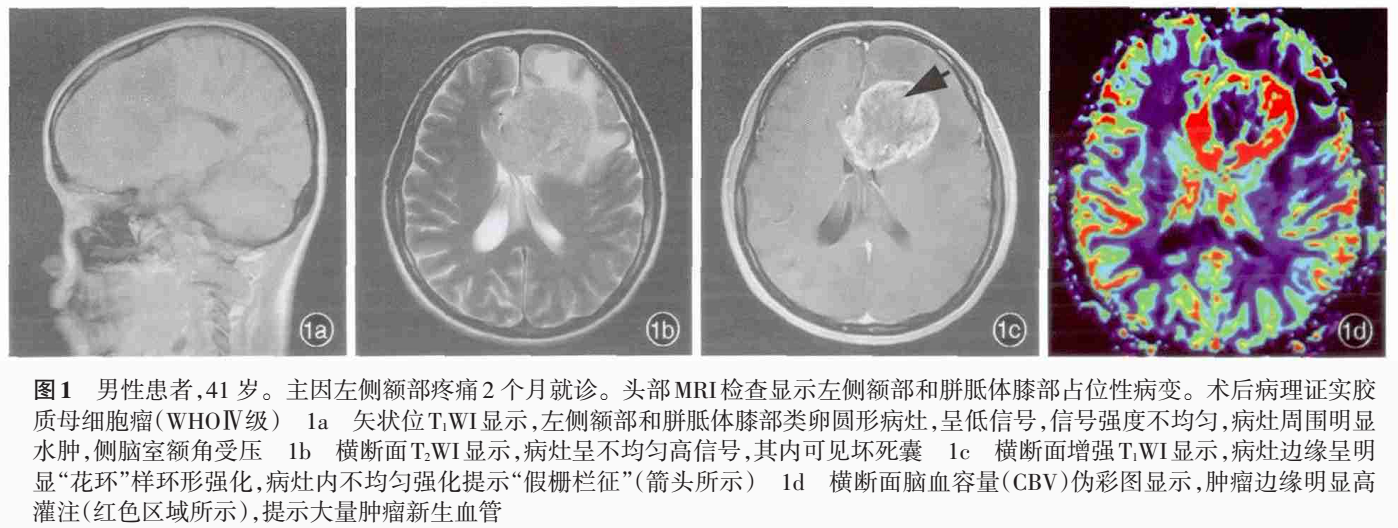

CT显示肿瘤呈边界不清的混杂密度影,常见瘤内出血所致高密度或囊性变、坏死;肿瘤跨胼胝体生长至对侧大脑半球时,呈“蝴蝶征”,水肿和占位效应明显。MRI在一定程度上能够揭示肿瘤的病理改变:T1WI呈不均匀低信号(图 1a),多合并坏死、囊性变或出血性改变;T2WI呈混杂高信号,中心坏死区为高信号,肿瘤生长区周围呈等信号,部分病变与肿瘤周围水肿分界不清,肿瘤内异常血管增生形成线样“流空效应”区(图 1b)。增强扫描肿瘤边缘呈显著对比强化,呈“花环”(ring/rim-enhancing)样(图 1c)、不规则环形、岛形或螺旋形改变;囊变性和坏死区周围肿瘤实质呈特征性“假栅栏征”,即圆形、椭圆形未强化区散在分布在强化区内,类似乳突蜂窝小房。DWI多呈高信号,ADC值明显减低。MRS提示NAA峰降低,Cho升高明显,MI峰较低级别星形细胞瘤低。灌注成像显示,病灶周围和病灶内有多处高灌注区(图 1d),提示大量肿瘤血管生成。胶质母细胞瘤虽具典型影像学特征,但仍需注意与颅内单发转移瘤、间变性胶质瘤、淋巴瘤等肿瘤性病变,以及脑脓肿、结核瘤、脱髓鞘假瘤等非肿瘤性占位性病变相鉴别。